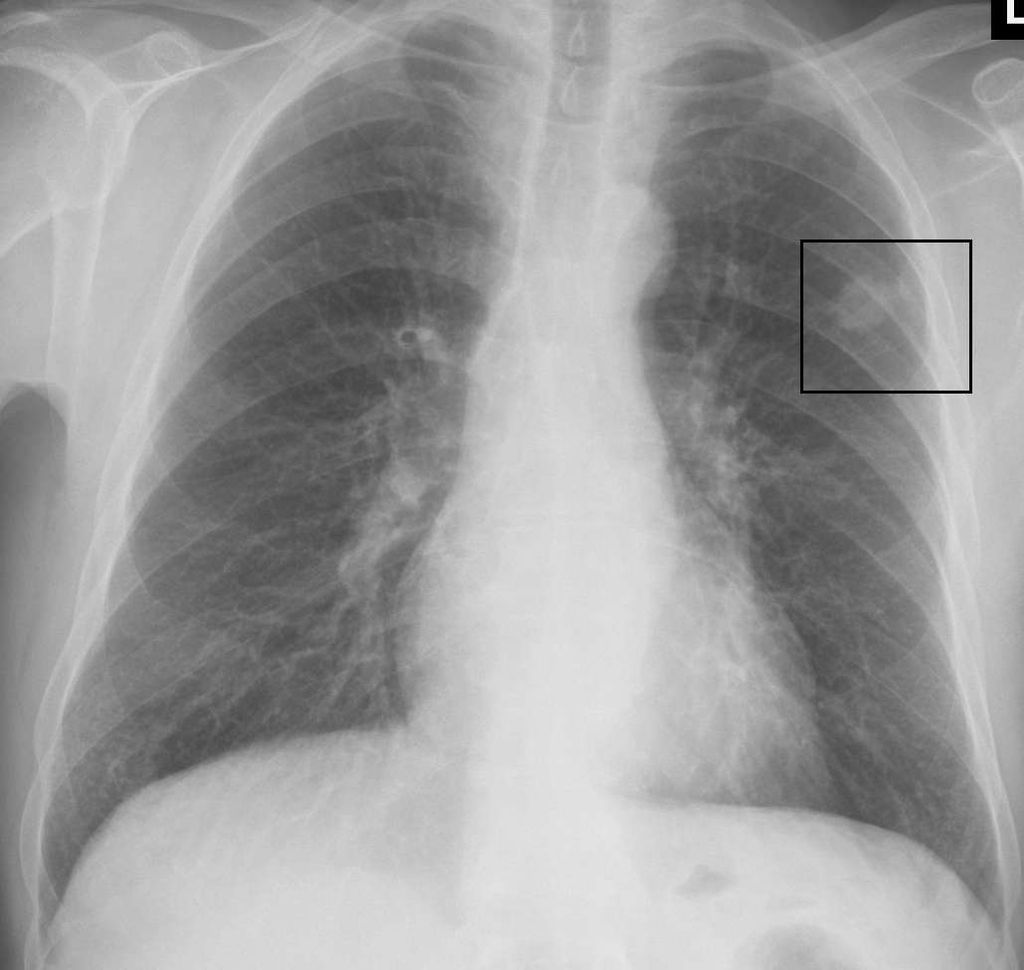

- Nodules pulmonaires: causés par des infections, une inflammation ou une croissance anormale.

Caractéristiques d’imagerie : des bordures irrégulières ou des caractéristiques internes spécifiques observées sur des échographies, des tomodensitogrammes ou des IRM peuvent suggérer un potentiel de malignité.